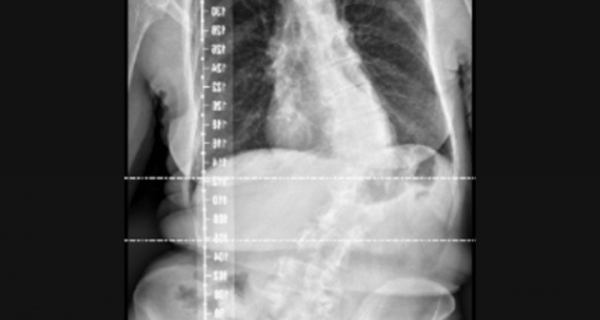

This case series reviewed adults with scoliosis who were treated using custom-designed ScoliBrace® orthoses, alongside targeted rehabilitation. The patients presented with varying curve types and severities, with goals focused on pain reduction, postural improvement, and curve stability.

Each brace was designed using 3D body scanning and tailored to optimise alignment while promoting functional correction. Patients were monitored regularly, with outcomes measured through radiographic Cobb angle changes, postural photographs, and quality-of-life assessments.

- Curve Management: Bracing contributed to stabilisation or improvement of Cobb angles, reducing the risk of progression in adulthood

This case series reinforces the role of custom, full-time or part-time bracing in managing adult scoliosis. The main results were improvement of coronal and sagittal balance, which are both linked to improving quality of life and reducing pain, and stabilisation of Cobb angles.